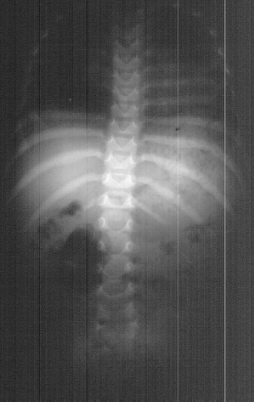

Radiographic evaluation at age of 3 showed mild scoliosis

and bilateral dislocated hips.

Age 6 scoliosis progressed to 78 degrees